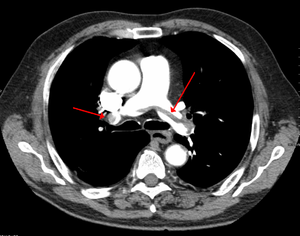

Pulmonary emboli. Reference. 위키백과